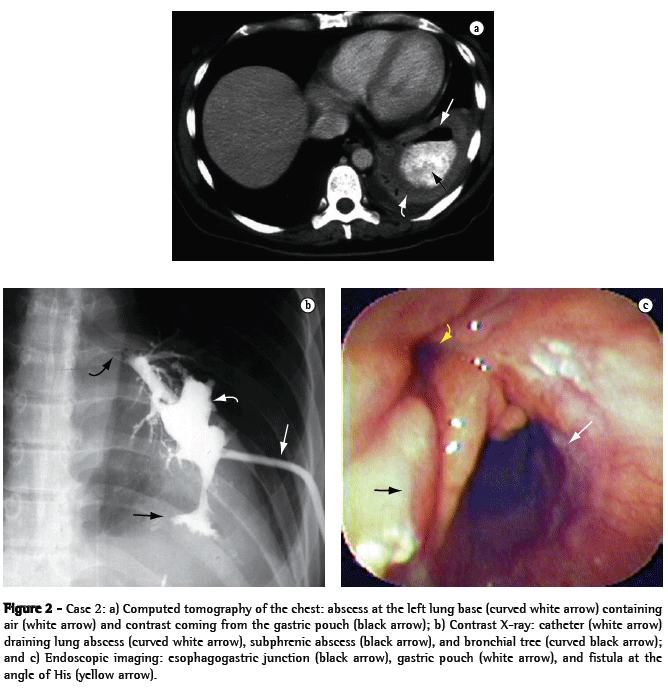

A 44-year-old female patient who underwent vertical banded gastroplasty (sleeve gastrectomy) by laparoscopy developed gastric fistula and presented five episodes of subphrenic abscess over an 8-month period. Her clinical symptoms began with pain in the left shoulder and worsened to include fever, cough, leukocytosis, worsening of overall health status, and excessive weight loss. The last two episodes were accompanied by cough with purulent expectoration, and computed tomography of the chest diagnosed an abscess at the left lung base (Figure 2a), secondary to subphrenic abscess at the angle of His, and gastric stenosis at the level of the band and the incisura angularis. The lung abscess resulting from the gastrobronchial fistula was drained through a catheter seen on a contrast X-ray (Figure 2b), and endoscopic imaging showed the internal opening of the fistula at the angle of His (Figure 2c).